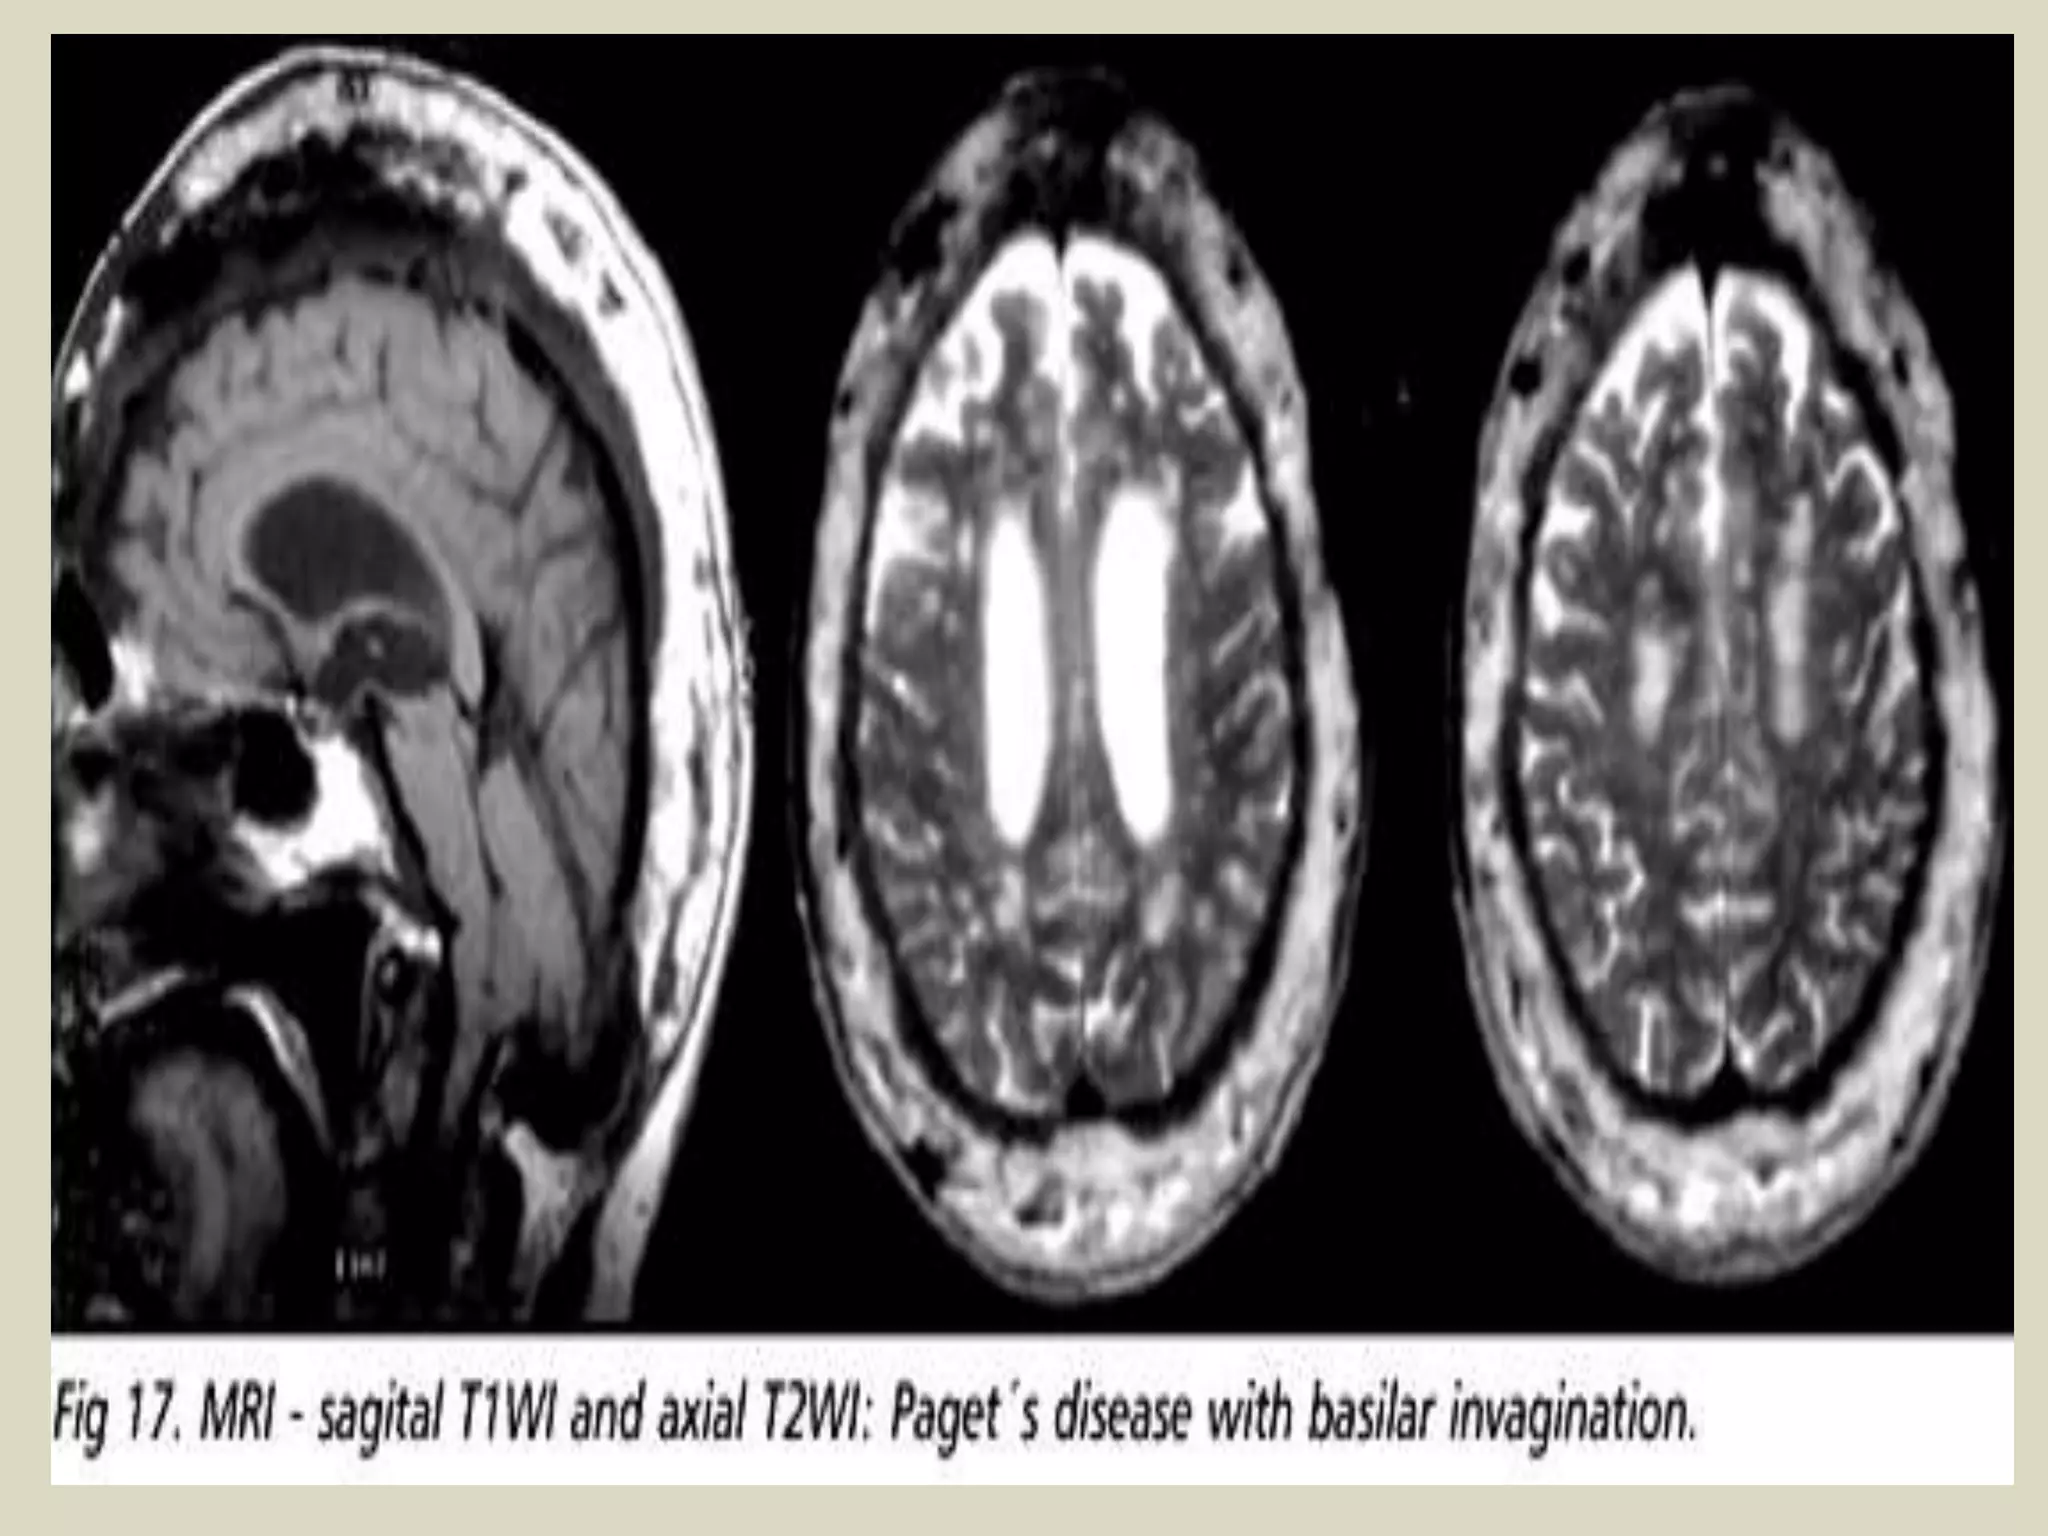

Paget disease complicated with basilar impression in 65-year-old woman. Sagittal T1-weighted MR

image (TR/TE, 500/16) displays basilar impression and compression of anterior aspect of pons. Note

marked deformity of tip of odontoid process that may be related to pagetic process. Cerebellum (C) is

also compressed. Basilar impression is diagnosed when tip of odontoid process (arrow) projects more

than 5 mm above Chamberlain line, which is drawn from hard palate (HP) to basiocciput (O). Calvaria

(arrowheads) appears expanded and displays heterogeneous, predominantly low signal intensity.